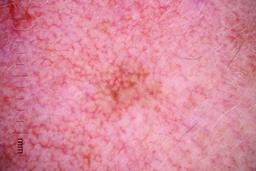

Description:

These are the images used in the paper: Analysis of the ISIC image datasets: Usage, benchmarks and recommendations

Paper Link: https://www.sciencedirect.com/science/article/pii/S1361841521003509

They have also been used by newer versions such as: Skin Lesion Classification Using Dermoscopic Images and Clinical Metadata: Insights from Multimodal Models